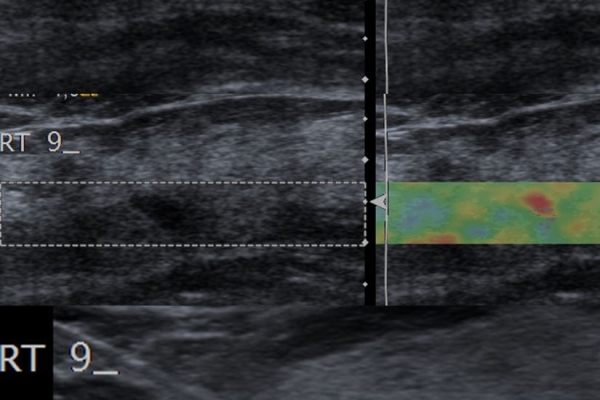

Η ελαστογραφία μαστού είναι μια σύγχρονη υπερηχογραφική μέθοδος που επιτρέπει τη διάκρισητων καλοήθων ογκιδίων από τους κακοήθεις όγκους.

Συνοπτικά ασκείται μια μικρή πίεση στους εντοπισμένους όγκους, μετρώντας την ελαστικότητα τους.

Ο καρκίνος γενικά εμφανίζει μεγαλύτερη σκληρότητα-ελαττωμένη ελαστικότητα σε σχέση με τα καλοήθη ογκίδια και επομένως η ελαστογραφία μπορεί να δώσει τις αναγκαίες πληροφορίες έτσι ώστε να μειώσει τις βιοψίες μαστού μόνο στις απολύτως απαραίτητες.